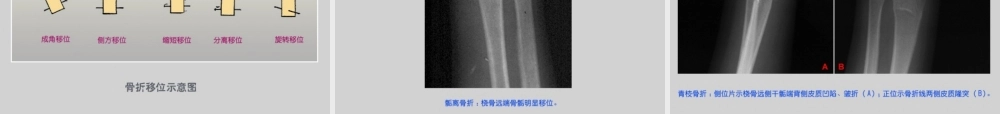

骨与关节创伤本节应了解、熟悉和掌握的知识点1.掌握骨骼、关节各种类型骨折的影像学表现2.熟悉骨关节损伤的CT和MRI影像学表现3.了解骨折愈合的病理组织学变化本节学习中的难点1.四肢和脊椎骨折的类型、判断骨折移位的标准及儿童骨折的特点,认识和掌握这些基本病变的X线表现对疾病诊断是重要的2.各种检查方法的成像原理及临床应用骨与关节创伤是常见病,影像学检查是主要手段X线平片是最简便有效而常用的方法MRI可直接显示软组织CT适于检查复杂结构3.1骨骼的创伤影像学检查目的:有无骨折或肌腱韧带断裂;了解骨折错位情况;需要时可在透视下行复位治疗;复位后拍片,了解复位情况;定期复查观察愈合情况和有无并发症;轻微外伤引起的骨折,应判断有无病理骨折;了解骨折是否累及关节;了解关节是否有脱位和关节软骨损伤(一)骨折总论骨组织的连续性中断称为骨折X线片上呈不规则的透明线称为骨折线骨皮质显示清楚松质骨表现为骨小梁连续性中断、扭曲或嵌插骨折以长骨和脊椎骨常见(1)长骨骨折定义:是骨或软骨结构发生断裂,骨的连续性中断,骨骺分离也属骨折。影像学表现基本X线表现:骨多为不整齐的断裂,X线上呈不规则透亮线,即骨折线,于皮质显示清楚整齐,在骨松质表现为骨小梁紊乱、扭曲、错位。严重骨折可使骨变形。嵌入性或压缩性骨折骨小梁紊乱,可局限出现密度增高的条带影,可能看不到骨折线。骨折的类型:根据骨折的程度可分为完全性和不完全性;根据骨折线的走向和形态,分为横行、斜行、螺旋形。复杂骨折的又可按骨折线形状分为T型、Y型等。根据骨碎片情况可分为撕脱性、嵌入性和粉碎性骨折。骨折的对位和对线关系:完全性骨折,要注意确定骨折断端的移位。骨折可发生内外、前后的移位,上下断端亦可相互重叠或分离。骨折端可以成角和旋转移位。骨折断端内外、前后和上下移位称为对位不良,而成角移位称为对线不良。骨折断端的嵌入:骨折断端相互嵌入,形成嵌入性骨折。X线片上并不显示透明的骨折线,表现为条带状密度增高影,系因相互嵌入的骨折端重叠所致。嵌入性骨折可引起骨骼的缩短与变形,移位不明显。嵌入骨折以股骨颈部多见。儿童骨折的特点:骺离骨折—骨折发生在儿童长骨,由于骨骺尚未与干骺端结合,外力可经过骺板达干骺端而引起骨骺分离。X线上只显示为骺线增宽或骺与干骺端对位异常。青枝骨折—在儿童,骨胳柔韧性较大,外力不易使骨质完全断裂,仅表现为局部骨皮质和骨小梁的扭曲,...